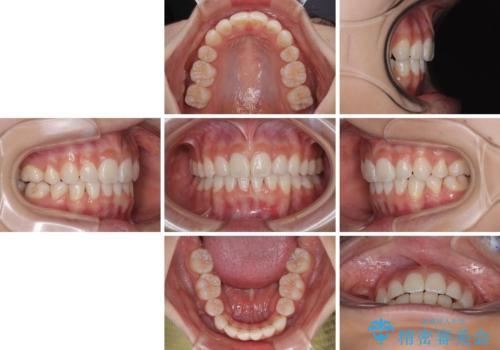

下唇に前歯が当たって跡が残ってしまう状態でしたが、スッキリとした口元に仕上げることができました。

- 口を閉じたときに飛び出してしまう上顎前歯を気にして来院された患者様です。

下顎はデコボコが気になっていたため、上下左右第一小臼歯4本を抜去して、ワイヤー装置にて口元の突出感を改善するよう矯正治療を行うこととしました。